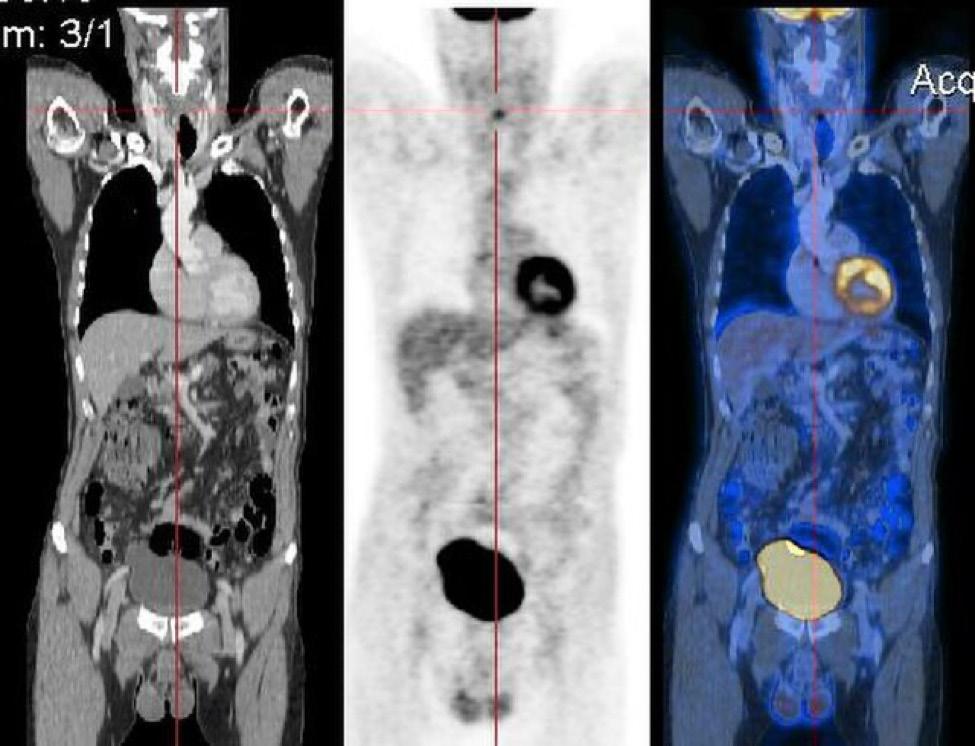

PET/CT is an imaging method that combines CT with PET to provide detailed information about both the structure (CT) and the function (PET) of cells and tissues in the body. The overlaying helps the radiologist be confident that a region of concern is cancer, such as when the CT and PET images line up. An example of a PET/CT overlay is shown in Graphic B. Magnetic resonance imaging (MRI) is a scanning technique that uses magnets and radio waves to generate images of the organs in the body (see Graphic C). It does not use X-rays. Sometimes the test is used with contrast. Other times it is not. MRI is the best test for imaging the brain. Because melanoma often

Graphic B. CT (left most panel), PET scan (center panel), and PET/CT (right panel) showing the overlain results. Reproduced from Wikimedia Commons, courtesy of Creative Commons Attribution.